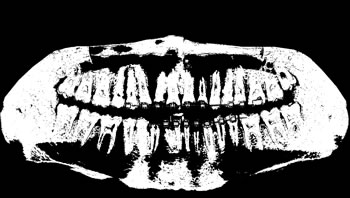

To thoroughly benchmark the methods studied here, the 1,500 images were distributed among 10 categories. The images were named, using whole numbers, in sequential order by category, aiming at not identifying the patients in the study. The process of categorizing the images was performed manually, selecting images individually, counting tooth by tooth, as well as verifying structural characteristics of the teeth. The images were classified according to the variety of structural characteristics of the teeth (see Table 5). Finally, the images were cut out to disregard non-relevant information (white border around the images and part of the spine) generated by the orthopantomograph device. After the clipping process, there was a change in the size of the images to 1991 ×\times 1127 pixels, but without affecting the objects of interest (teeth), as shown in Figure 2. The cropped images were saved on the new dimension to be used in the following stages, which will be presented in the next sections. Figure 3 shows an X-ray image corresponding to each of the categories of our data set.

Refer to caption

Figure 2: Example of the clipping and resizing of the data set images of the present work.